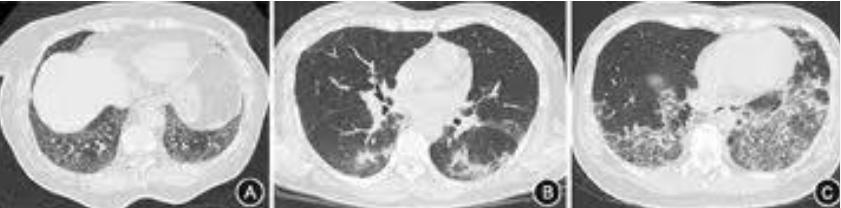

ASS-ILD患者HRCT表现在轴面分布特点以外周为主,冠状面主要在基底部分布,肺间质疾病的影像学类型以NSIP为主,其次是NSIP-OP。NSIP-OP是一种混合型ILD类型,即在NSIP背景上出现典型的OP,NSIP-OP的影像表现在其他ILD中相对少见,影像学表现NSIP-OP时,应寻找是否有抗合酶抗体的存在。

A:76岁女性,CT表现为双下肺为主的磨玻璃影、网格影,符合NSIP;B、C:同一患者46岁女性,B显示双肺下叶背段支气管血管束周围斑片状实变影,左侧呈反晕征,符合OP;C为稍下层面显示双肺下叶基底段磨玻璃影、网格影,符合NSIP,该患者影像表现为NSIP-OP;D:72岁女性,CT显示双下肺蜂窝影,符合UIP。ASS临床表现主要包括:肌炎、ILD、多关节炎、技工手、发热及雷诺现象。多项研究发现ILD是最常见的表现。特发性炎性肌病(IIM)患者中抗Jo-1抗体阳性ASS患者的关节炎发生率(64.2%)高于阴性者(18.1%)。ILD是ASS发病率和死亡率的主要决定因素。ASS-ILD可表现为ARDS和难治性呼吸衰竭,可于临床中任何时间发生。对于疑诊ILD,应使用HRCT和肺功能检查早期确诊。肺活检对明确ILD病因至关重要且可指导治疗。特发性炎性肌病常被分为多发性肌炎、皮肌炎和包涵体肌炎。大多数ASS患者既往会被分类为皮肌炎。10多年前只有少数肌炎包含相关的自身抗体,新的特异性自身抗原的发现成为此领域的一个重要进展,抗合成酶抗体(anti-synthetase antibody,ARS)阳性代表一种被称为抗合成酶综合征(ASS)的表型。抗组氨酰tRNA合成酶(JO-1)抗体(60%~80%)最为常见,其他还包括抗PL-7抗体(10%~15%)、抗PL-12抗体(5%~15%)、抗EJ抗体、抗OJ抗体(5%)、抗KS抗体、抗Zo抗体等。ASS治疗除治疗肌炎外,还应强调对ILD的治疗,主要是糖皮质激素和免疫抑制剂。激素能够抑制炎症、免疫反应及抑制增殖过程,对以炎症为主的早期ILD有效,通常作为首选药物。免疫抑制剂、激素是治疗ASS的主要药物,联合免疫抑制剂治疗可以最大限度地控制疾病进展,主要药物包括硫唑嘌呤(AZA)、甲氨蝶呤(MTX)、环磷酰胺(CYC)、环孢素等。也有研究表明,加用抗纤维化药物(如吡非尼酮)对于肺功能改善也有一定疗效。对于一些难治性患者,可使用免疫球蛋白、利妥昔单抗、肺移植等治疗方法。对于ILD,一定要注意查体和病史采集,科间协作有利于ILD的诊断和治疗。部分结缔组织病合并间质性肺炎即时采取ECMO救治有效,能够改善患者预后。痰培养、ROSE、NGS联合应用对于病原学早期精确诊断具有较大价值。CRE治疗应遵循早期精准的策略,《鲍曼不动杆菌感染诊治与防控专家共识》中CRAB治疗中舒巴坦剂量4g以上,根据PK/PD指导原则:头孢哌酮舒巴坦3g q6h疗效显著。青霉素皮试可能出现假阳性,不能绝对指导临床药物选择。此外,团队合作,包括医师、护理、RT、康复治疗师等,在重症患者的抢救中也至关重要。